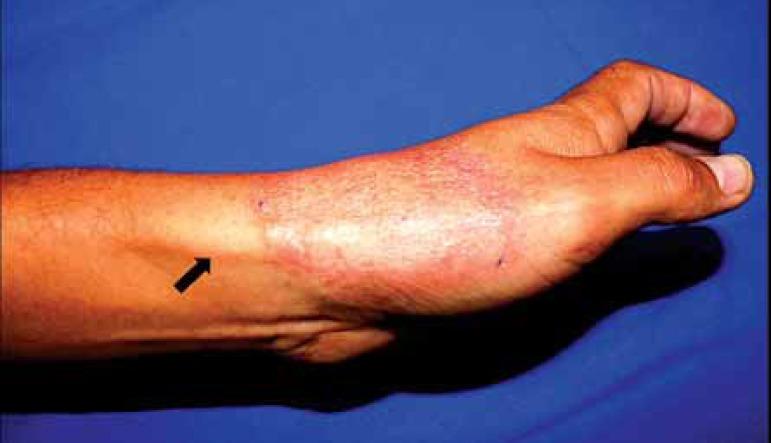

Tuberculoid leprosy presenting as a "racket" lesion.

The "racket" lesion is a rare presentation of tuberculoid leprosy, which consists of a thickened nerve branch emerging from a tuberculoid plaque. It results from centripetal damage to cutaneous nerves caused by granuloma formation. We describe a typical case of tuberculoid leprosy presenting as a "racket" lesion. The lesion persisted after treatment with paucibacillary multidrug therapy.